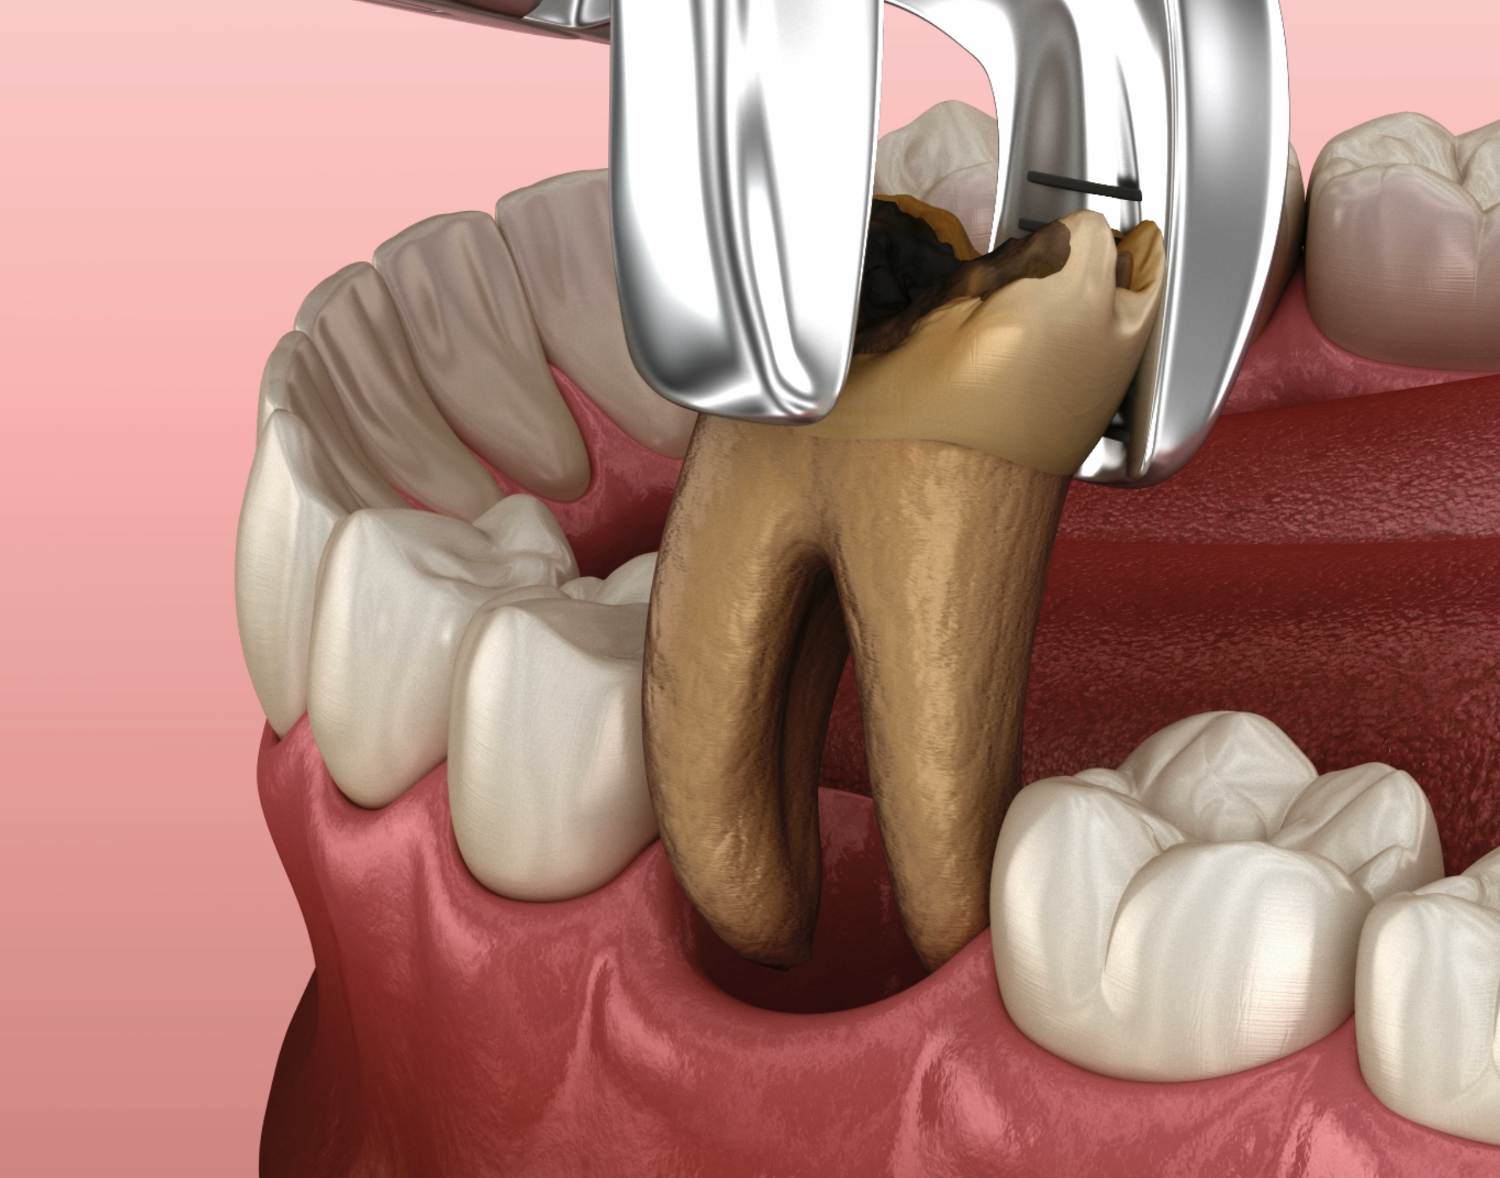

Tooth Extraction Procedure Aftercare Recovery best sale, Surgical extraction of mandibular third molar a rational and safe best sale, Dental extraction Wikipedia best sale, From Start To Finish How Long Does A Tooth Extraction Take best sale, Dry Socket What It Is Symptoms Treatment best sale, Upper right 1st molar extraction with interradicular septum. A best sale, Dental extraction Wikipedia best sale, Tooth Extraction Home Care Instructions Cobblestone Dental Care best sale, Los Angeles Wisdom Tooth Extraction Questions Dr. Jamie Sands best sale, Tooth extraction Information Mount Sinai New York best sale, Physics Forceps Upper Molar Tooth Extraction Cytoplast Barrier Grafting best sale, Tooth Extractions Milton FL Thrive Dental Associates best sale, Why Replace A Back Molar Marietta Tooth Replacement Muskingum best sale, Your Guide To Surgical Tooth Extraction Grand Central Dentistry best sale, Complications of Dental Extractions Geeky Medics best sale, The Beginner s Guide to Tooth Extraction Family Choice Dental best sale, Tooth Extractions Drexel Hill PA Bloomfield Dental best sale, Comparing Tooth Extraction vs Root Canal What s the Difference best sale, Tooth Extraction best sale, Tooth Extraction Boston MA Dentist James M. Stein DMD best sale, Tooth Extraction Removal Bupa Dental Care UK best sale, Tooth Extraction Cost for 2021 Procedure Risks Recovery best sale, Wisdom Tooth Extraction Removal Procedure Pain Cost Recovery best sale, Healing of local gingival tissue following tooth extraction best sale, What Happens When You Have To Extract and Replace a Molar Spear best sale, Asymmetrical Extraction in an Adult Class II best sale, Tooth Extraction Dr. Christian Chung D.D.S best sale, Tooth Extractions Moorehead Dentistry Batavia OH best sale, Oral Surgery in NYC Tooth Extraction 209 NYC Dental best sale, Dental extraction Wikipedia best sale, Tooth Extractions best sale, Badly Infected Tooth Extraction Procedure With Pus Coming Out of The Tooth best sale, Fast Tooth Extractions at a Great Price Lake Lanier Smiles best sale, Treatment Options After Tooth Extraction best sale, What you need to know before a tooth extraction Top Doctors best sale.

Tooth Extraction Procedure Aftercare Recovery best sale, Surgical extraction of mandibular third molar a rational and safe best sale, Dental extraction Wikipedia best sale, From Start To Finish How Long Does A Tooth Extraction Take best sale, Dry Socket What It Is Symptoms Treatment best sale, Upper right 1st molar extraction with interradicular septum. A best sale, Dental extraction Wikipedia best sale, Tooth Extraction Home Care Instructions Cobblestone Dental Care best sale, Los Angeles Wisdom Tooth Extraction Questions Dr. Jamie Sands best sale, Tooth extraction Information Mount Sinai New York best sale, Physics Forceps Upper Molar Tooth Extraction Cytoplast Barrier Grafting best sale, Tooth Extractions Milton FL Thrive Dental Associates best sale, Why Replace A Back Molar Marietta Tooth Replacement Muskingum best sale, Your Guide To Surgical Tooth Extraction Grand Central Dentistry best sale, Complications of Dental Extractions Geeky Medics best sale, The Beginner s Guide to Tooth Extraction Family Choice Dental best sale, Tooth Extractions Drexel Hill PA Bloomfield Dental best sale, Comparing Tooth Extraction vs Root Canal What s the Difference best sale, Tooth Extraction best sale, Tooth Extraction Boston MA Dentist James M. Stein DMD best sale, Tooth Extraction Removal Bupa Dental Care UK best sale, Tooth Extraction Cost for 2021 Procedure Risks Recovery best sale, Wisdom Tooth Extraction Removal Procedure Pain Cost Recovery best sale, Healing of local gingival tissue following tooth extraction best sale, What Happens When You Have To Extract and Replace a Molar Spear best sale, Asymmetrical Extraction in an Adult Class II best sale, Tooth Extraction Dr. Christian Chung D.D.S best sale, Tooth Extractions Moorehead Dentistry Batavia OH best sale, Oral Surgery in NYC Tooth Extraction 209 NYC Dental best sale, Dental extraction Wikipedia best sale, Tooth Extractions best sale, Badly Infected Tooth Extraction Procedure With Pus Coming Out of The Tooth best sale, Fast Tooth Extractions at a Great Price Lake Lanier Smiles best sale, Treatment Options After Tooth Extraction best sale, What you need to know before a tooth extraction Top Doctors best sale.